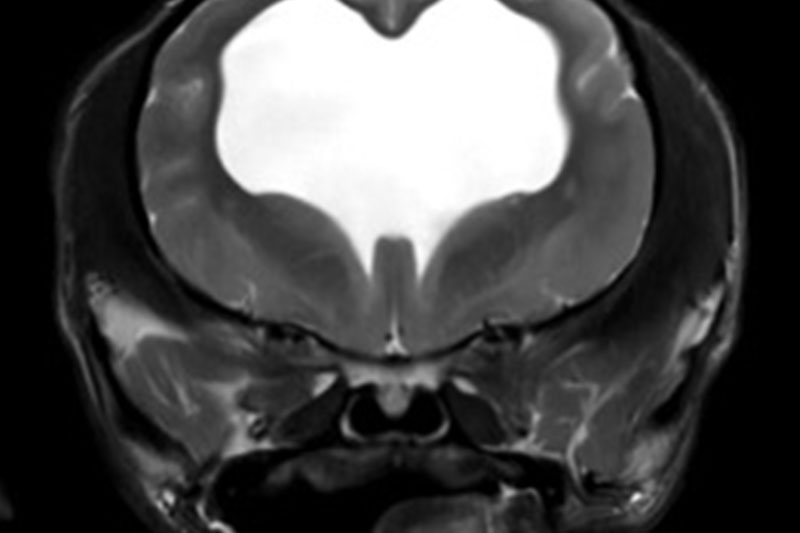

본 병원은 GE사의 1.5T 고해상도 자기공명영상장치(MRI)를 이용하여, 자기장을 이용한 비침습적 방식으로 뇌, 척수, 근골격계 등 다양한 연부조직을 정밀하게 영상화할 수 있습니다. MRI는 방사선을 사용하지 않아 반복 촬영에도 안전하며, 신경계 및 연부조직에 대한 탁월한 해상도를 제공하여 정확한 진단에 매우 유용합니다.

또한 본원의 MRI 장비는 GE사의 PROPELLER 기법을 도입하여 호흡이나 움직임에 따른 영상 왜곡을 최소화하면서도 검사 시간을 단축시켜, AI 기반 영상 처리 기술을 통해 노이즈를 줄이고 더욱 선명하고 명확한 영상을 획득할 수 있습니다. 이러한 기술적 강점을 바탕으로 마취 시간과 그에 따른 환자의 부담을 줄이면서도, 진단에 충분한 고화질 영상을 안정적으로 확보할 수 있습니다.